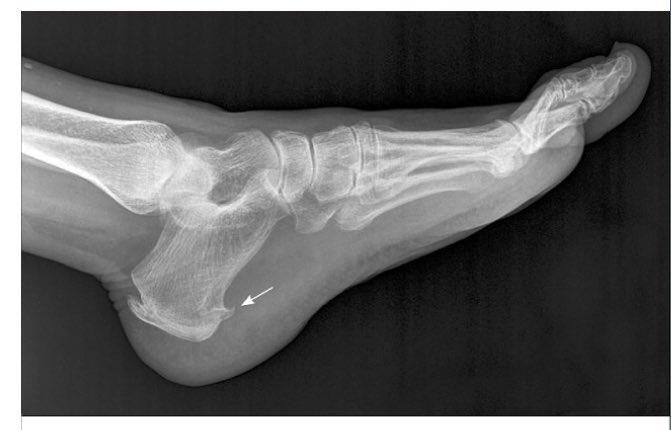

يشخص من خلال الفحص السريري ونادرا ما يحتاج إلى التصوير الإشعاعي.

أحيانا قد يكون السبب مسمار كعب القدم كما يظهر في الأشعة المرفقة.